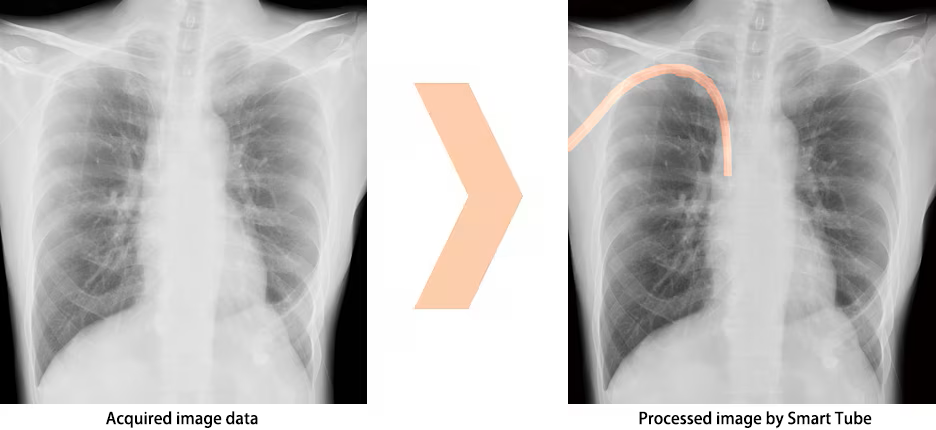

Smart Tube : Software zur Darstellung von Schläuchen und Kathetern OPTION

Smart Tube wurde mit KI-Technologie entwickelt und verbessert die Erkennung potenzieller Bereiche von Schläuchen und Kathetern anhand von Röntgenbildern, wodurch die Positionsüberprüfung unterstützt wird. *1)

Anzeige der von Smart Tube verarbeiteten Röntgenbilder *2)

Bildschirmdarstellung mit Smart Tube

- *1) Verlassen Sie sich bei der Überprüfung der dargestellten Bilder mit Schläuchen oder Kathetern nicht ausschließlich auf die Bildverarbeitungsfunktionen von Smart Tube. Treffen Sie Ihre endgültige Entscheidung anhand einer visuellen Überprüfung oder anderer Methoden.

- *2) Die in Smart Tube verwendete KI-Technologie (künstliche Intelligenz) ist keine selbstgesteuerte interaktive Lern-KI.